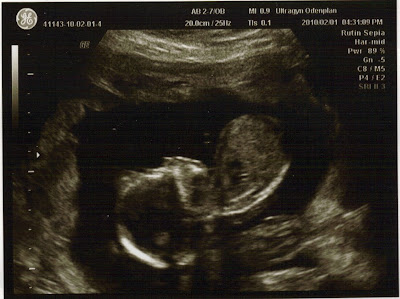

Hej dÀr inne i magen!